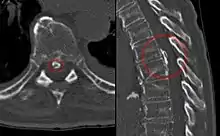

CT scan of the spine, showing calcification of the longitudinal posterior ligament.